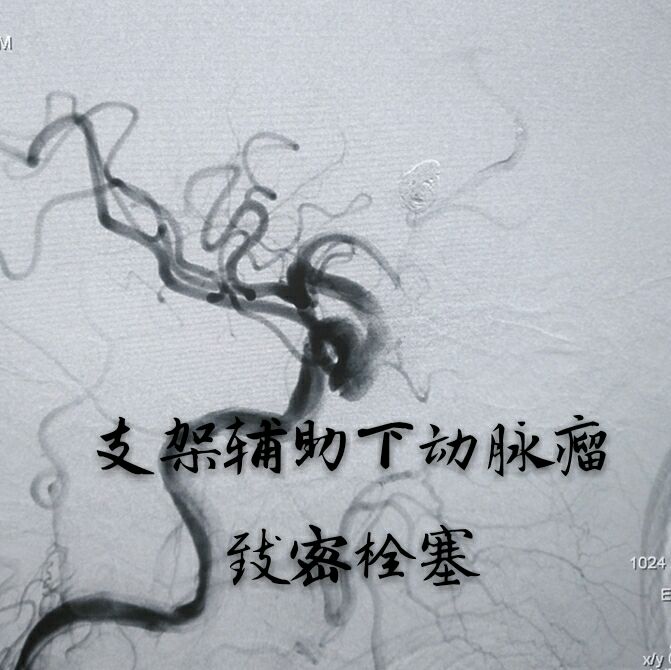

病例九:中年女性患者,间断性头痛3年,DSA示左侧大脑中动脉分叉部动脉瘤,累及上下干

支架辅助下动脉瘤致密栓塞,难点:当时没有3D工作站,动脉瘤与载瘤动脉的关系判断困难,最终通过反复观察3D旋转和造影解决了问题